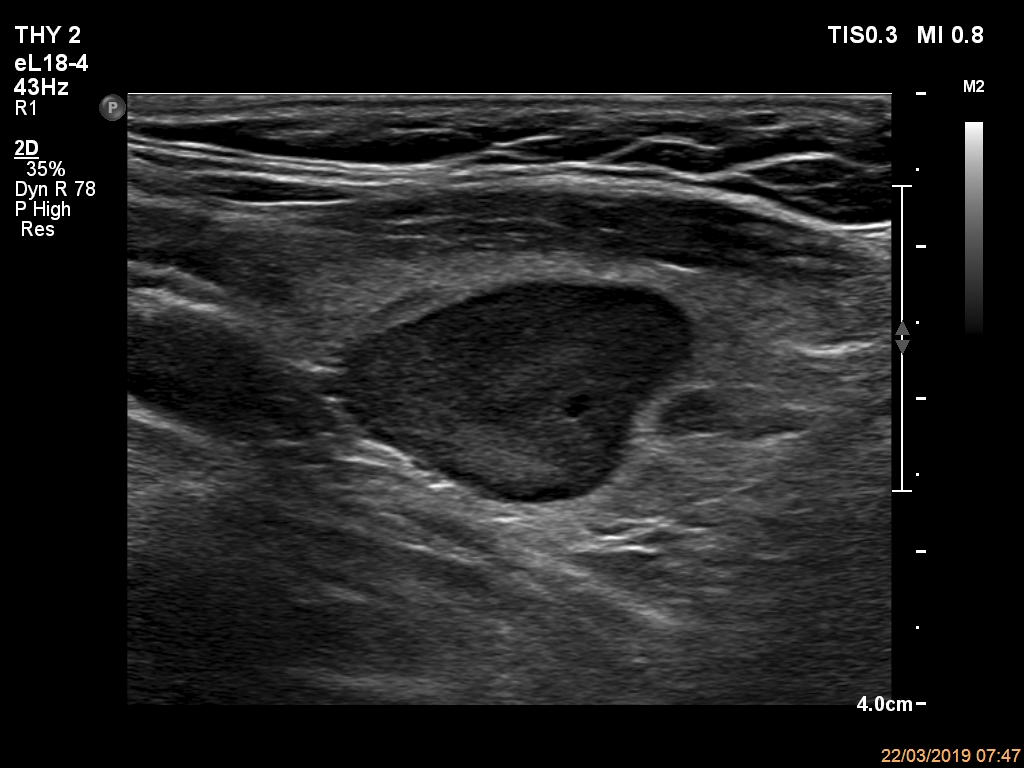

Elastography - case 2150 (ultrasonographic picture 9)

Left lobe, another longitudinal scan.